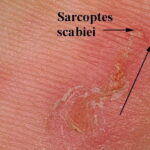

Burrows are the pathognomonic lesions of scabies and are found mostly in the florid, papulovesicular type of sarcoptic acariasis . They are produced by female mites and occur mainly on the palms and plantae, the palmar and lateral aspects of the fingers and toes, the interdigital spaces, the flexor surfaces of the wrists, the nipples of women, the genitals of men, and, to a lesser extent, on the buttocks and axillae. Characteristically, the head is spared, except in newborns and infants . The burrows appear as fine, tortuous, blackish threads a few millimeters long. A vesicle may be visible near the blind end of the burrow. The mite is situated in this vesicle and may be visible as a tiny gray speck by dermatoscopy. Although pathognomonic, the burrow is not the most common lesion seen in scabies. Small, erythematous, often excoriated papules are more frequent . |

Acarid mites produce several skin manifestations in humans, the most common one represented by scabies, which is caused by the eight-legged itch mite Sarcoptes scabiei var. nominis, also referred to as s. sarcoptes scabiei. Animal pathogenic mites also affect the skin, although only transiently because the mites do not survive for an extended period of time . |